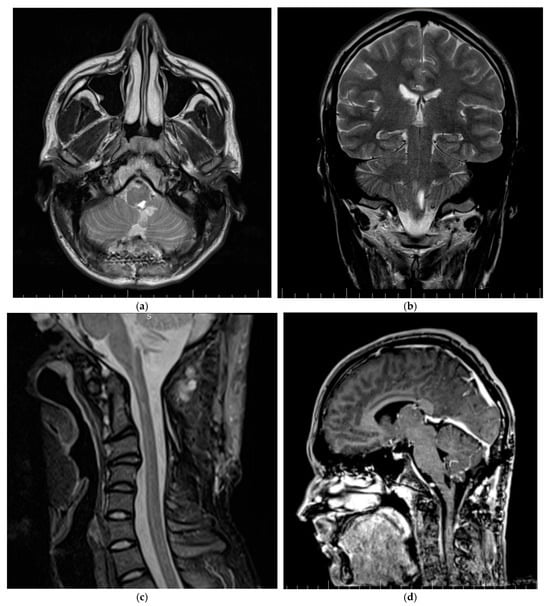

3.1.3. Patient Three